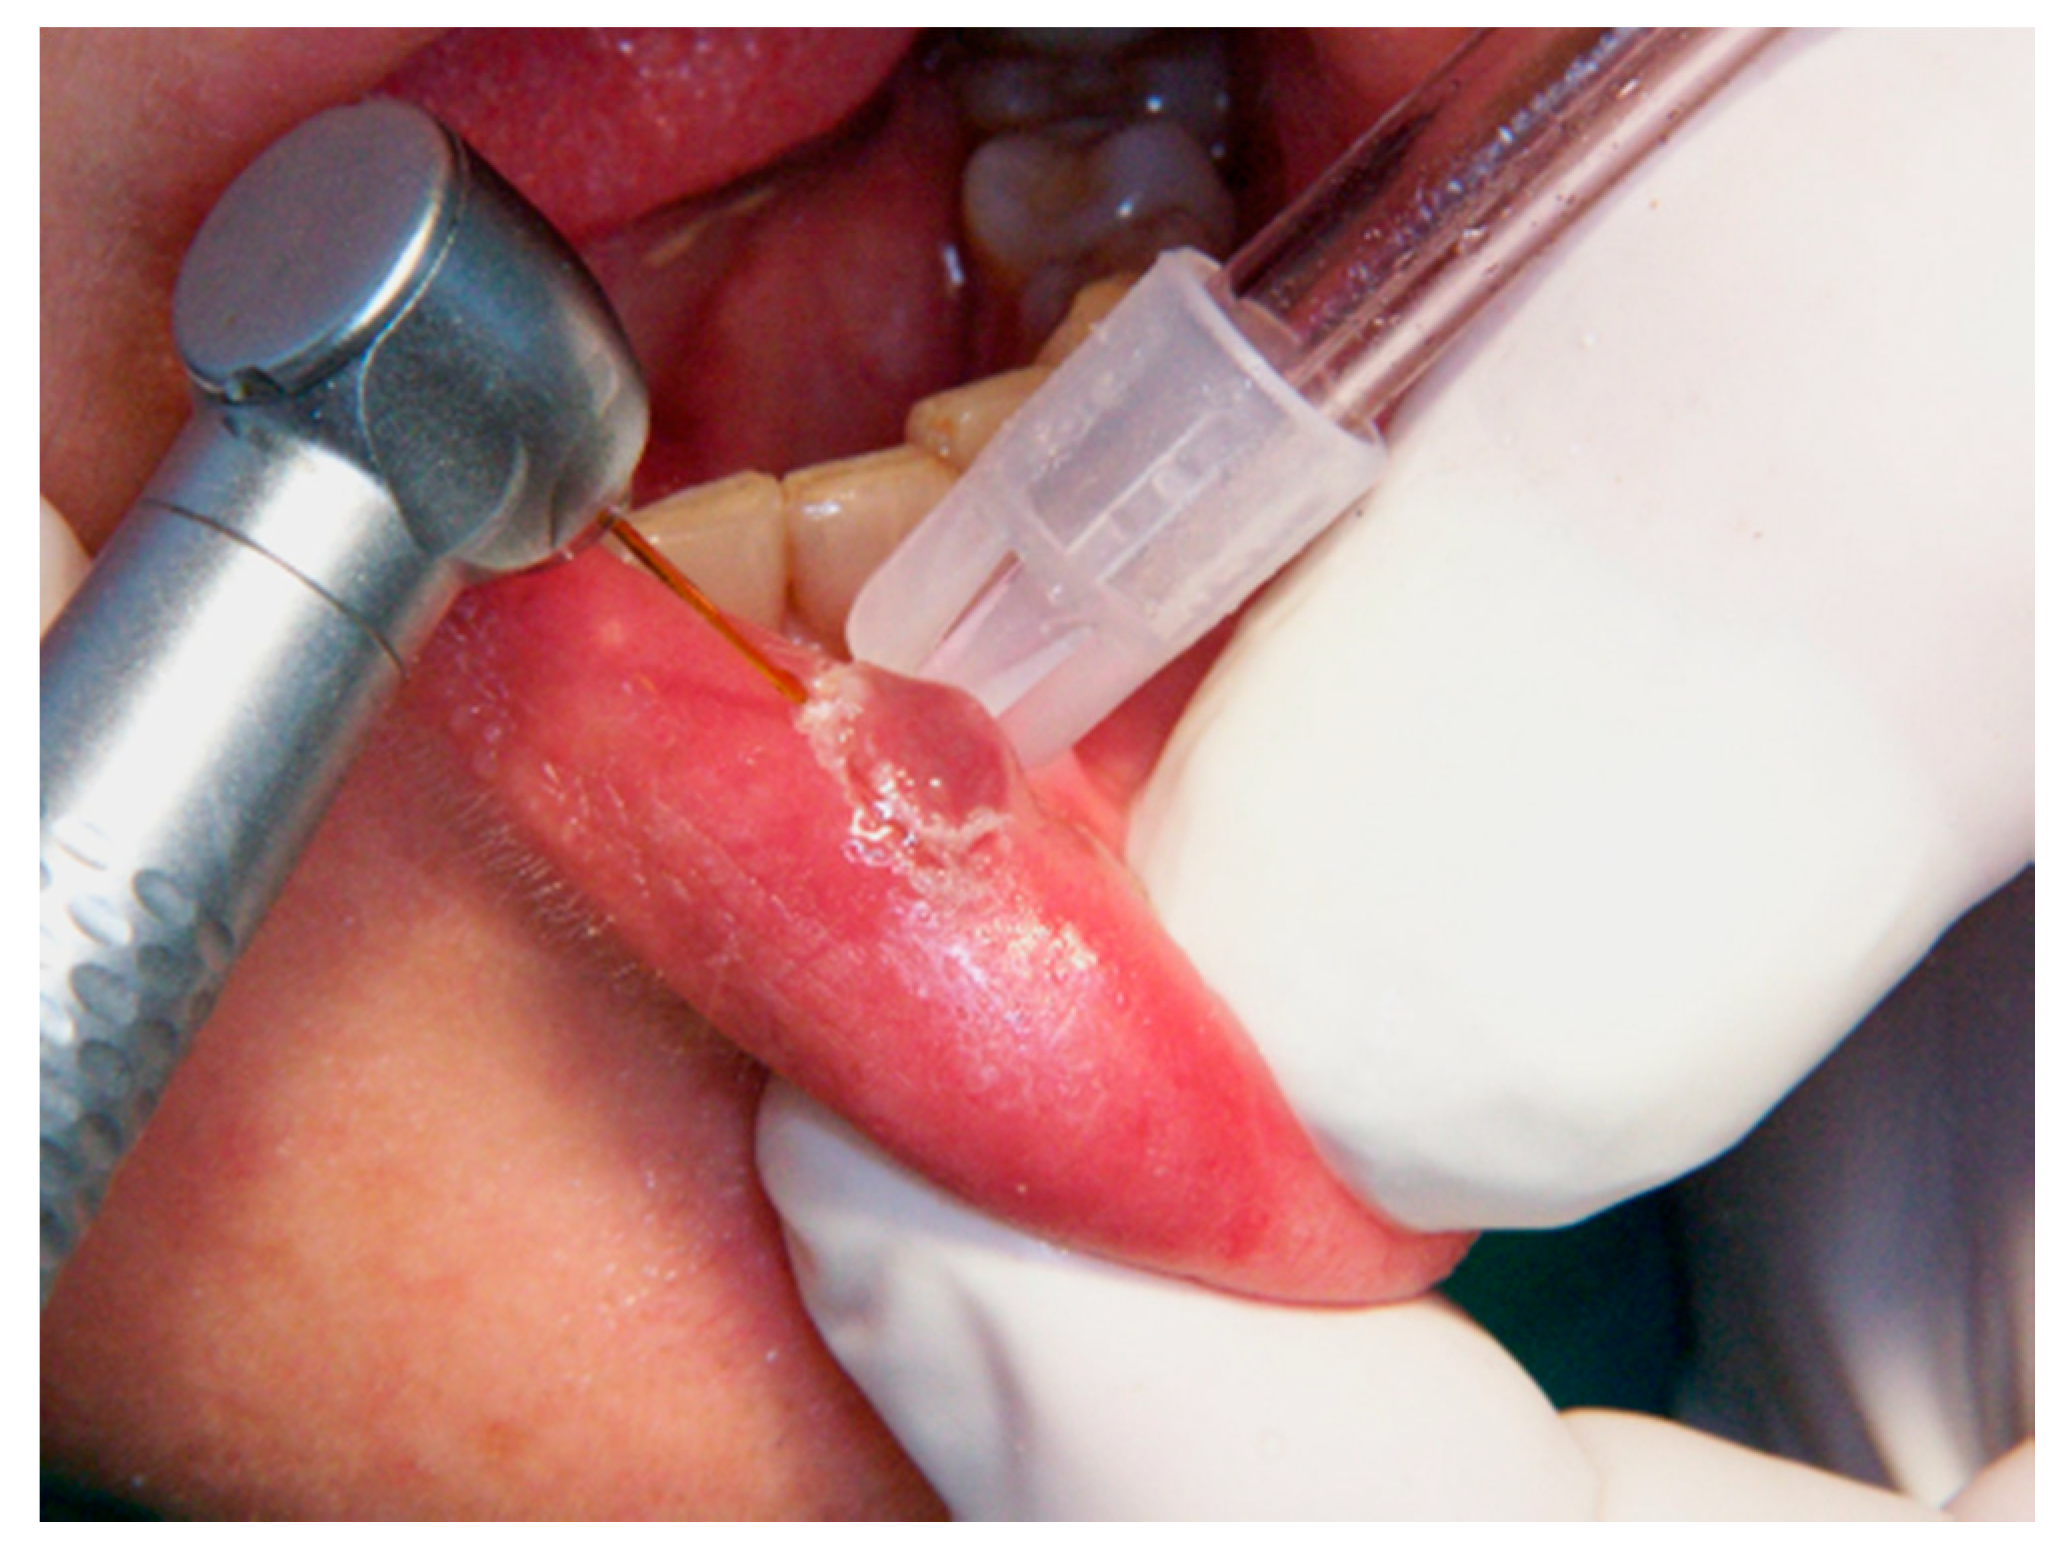

2.3.4. Diode Laser